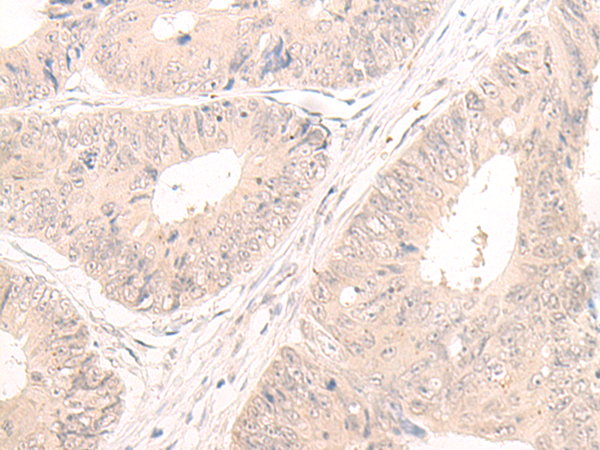

The image is immunohistochemistry of paraffin-embedded Human colorectal cancer tissue using 47257(LCMT2 Antibody) at dilution 1/55.(Original magnification: 200)